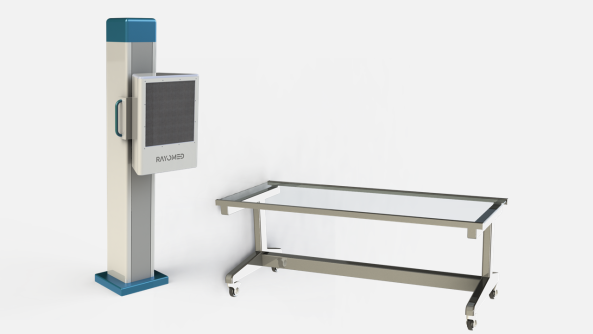

حالت تک دتکتور

حالت دو دتکتور

در حالت تک دتکتور، یک تخت پرتابل و یک استند با قابلیت دوران به همراه دتکتور ارائه خواهد شد که استند این قابلیت را دارد که دتکتور را در دو حالت ایستاده و خوابیده نگه دارد تا حالت های مختلف عکسبرداری قابل انجام باشد. این حالت برای مراکز تصویربرداری با مراجعین نسبتا کم مناسب می باشد.

در حالت دو دتکتور، یک تخت موتورایز شش جهته و یک استند موتورایز به همراه دو دتکتور ارائه خواهد شد و بدین ترتیب حالت های مختلف عکسبرداری با سرعت بیشتری قابل انجام است. این حالت برای بیمارستان ها و مراکز تصویربرداری بزرگ با تعداد مراجعین بالا مناسب است.